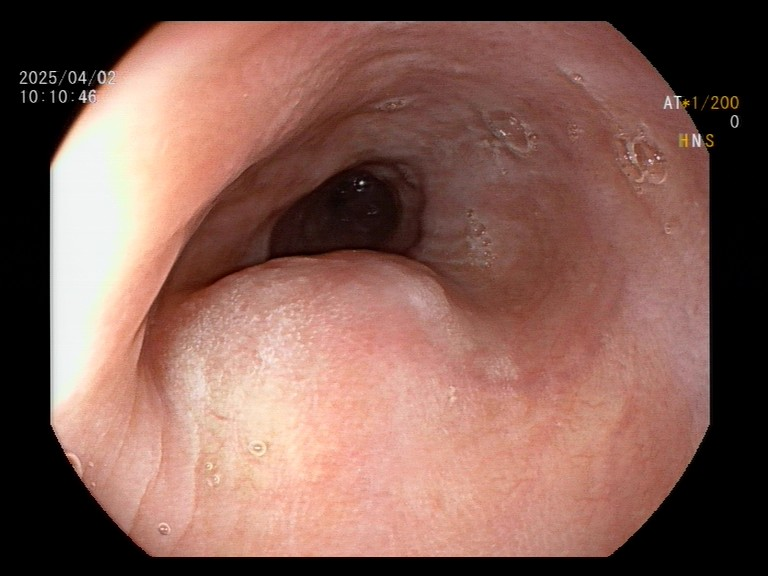

食管肿瘤管腔内凸起明显 面对这一棘手难题,涪陵区人民医院消化内科团队果断采用内镜黏膜下隧道技术(STER)。该技术通过在食管黏膜下构建一条“安全隧道”,巧妙地在大血管与食管粘膜下层之间开辟操作空间,既能完整剥离肿瘤,又能有效规避血管与神经风险。手术过程中,于劲教授凭借丰富的经验,现场展示了毫米级的精准剥离技艺:在内镜清晰视野下,以电刀小心翼翼地逐层分离瘤体与食管肌层。仅耗时2小时,便将肿瘤完整切除,术中出血量仅数毫升,同时完美保留了食管黏膜层,堪称“刀尖上的艺术”。